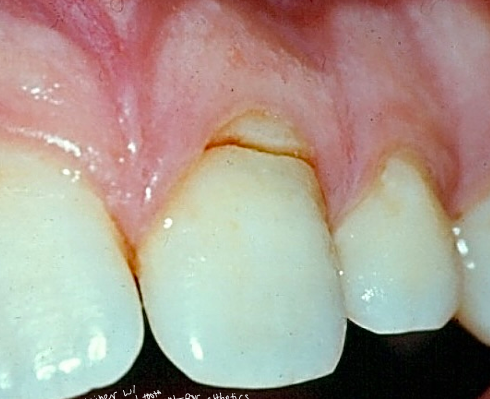

uncomplicated crown fracture

-enamel-dentin

-restorative procedures to treat

complicated crown fracture

-enamel-dentin-pulp

-apply concept 1: if root mature then remove the pulp/RCT, if root immature then preserve radicular pulp tissue